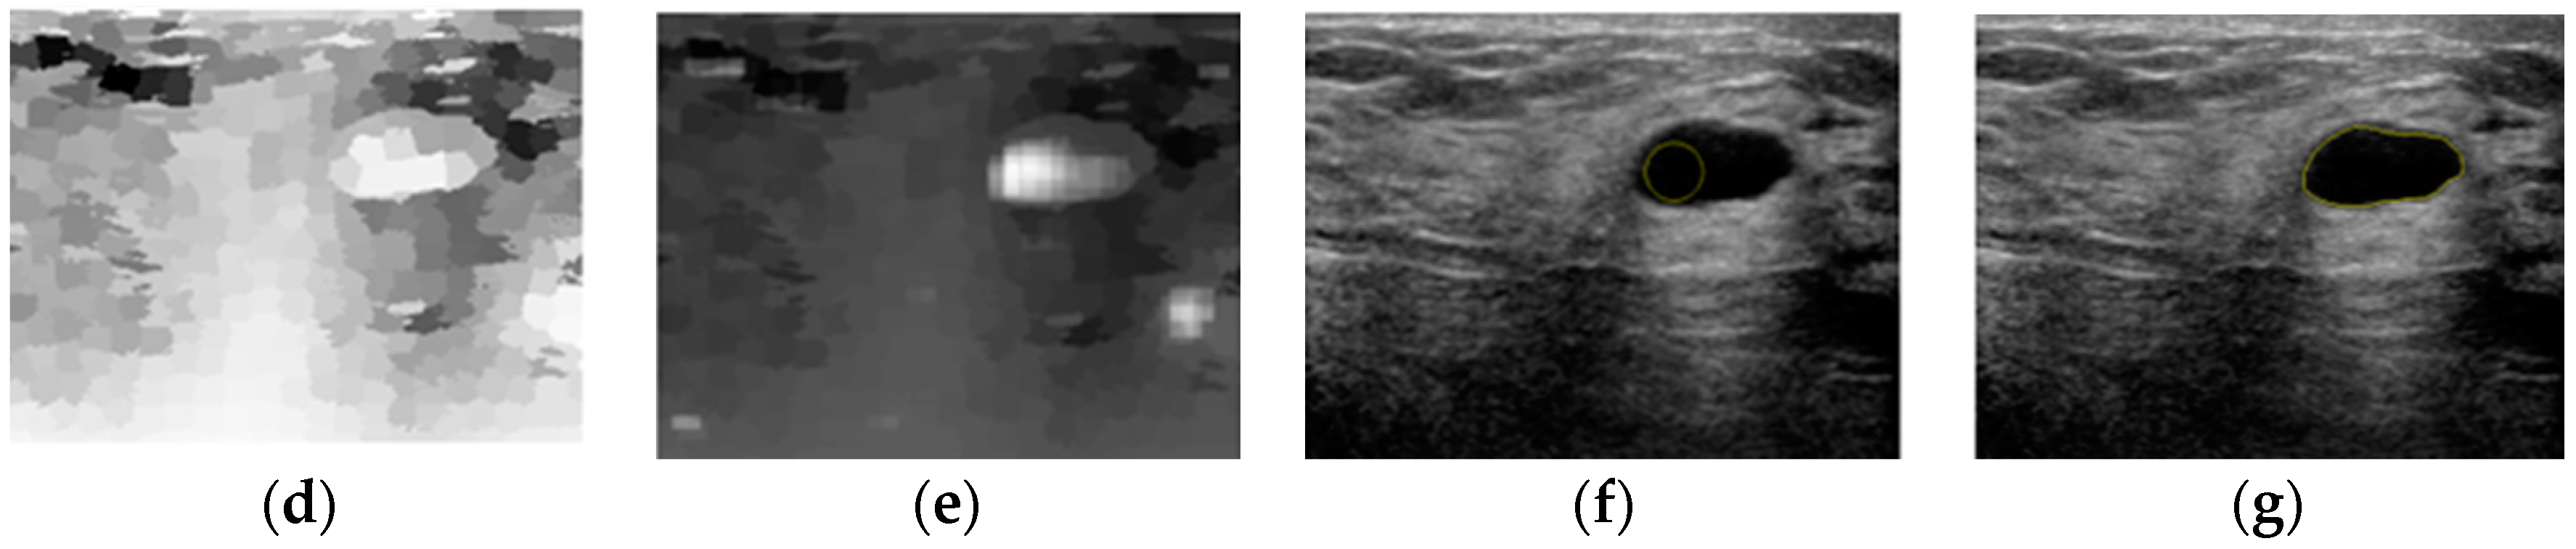

An Automatic Localization Algorithm for Ultrasound Breast Tumors Based on Human Visual Mechanism

Xie, Y.; Chen, K.; Lin, J. An Automatic Localization Algorithm for Ultrasound Breast Tumors Based on Human Visual Mechanism. Sensors 2017, 17, 1101. https://doi.org/10.3390/s17051101